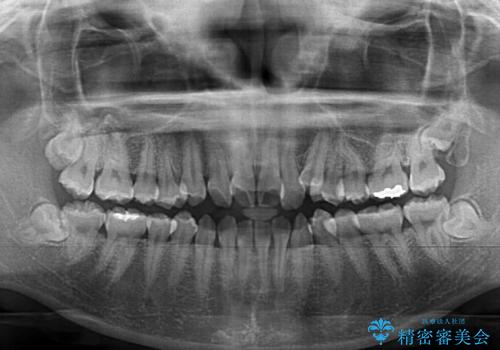

- 八重歯や前歯の捻転とクロスバイトが気になり、インビザラインによる矯正治療を希望して来院された患者様です。

上顎側切歯(上の真ん中から2番目の歯)が舌側転位している場合、無理して動かそうとすると歯髄壊死を起こすリスクが高い印象があります。

インビザライン単体でも治療は可能ですが、安全策としてインビザラインで歯列を移動する前に上顎前歯をワイヤー矯正で整え、その後上下歯列をインビザラインにて矯正治療を行うこととしました。